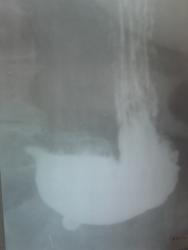

Больная с жалобами на тошноту, изжогу, боли в эпигастрии. Направлена на исследование желдука с диагнозом: хр. гастрит. Исключить ЯБ.

ФГДС сделать невозможно, больная 1932 г.р.

Обзорно в положении стоя получилось вот что:

обратил внимание что медиальнее малой кривизны, примерно на 3 см, появился контраст.

На снимке очень тяжело понять что я имел ввиду, так как вагон и маленькая тележка экранных артефактов (никак не могу "выбить" свежие кассеты)

Далее на малой кривизне увидел, что-то похожее на нишу:

Но при дальнейшем исселедовании выяснилось, что это не ниша, а маленький пульсионный дивертикул около 5-6 мм в диаметре, но почему-то я его не заснял.

В конце концов решил раздуть и посмотреть что будет )))

Вот что было:

И чуть потемнее:

Уважаемые коллеги, неужели это так раздулся дивертикул?

Немного не довернул на снимке. Но он с тонкой шейкой, небольших размеров.

А пунктиром обозначил то, что случилось после раздувания

Считаю, что это не дивертикул (вероятно отпечаток пальца при "зарядке" кассеты) - слишком тонкая ("призрачная") стенка; при раздувании

дивертикулы увеличиваются не так резко.

Все дело в том, в том что я это видел на экране скопии и потом сделал снимок.